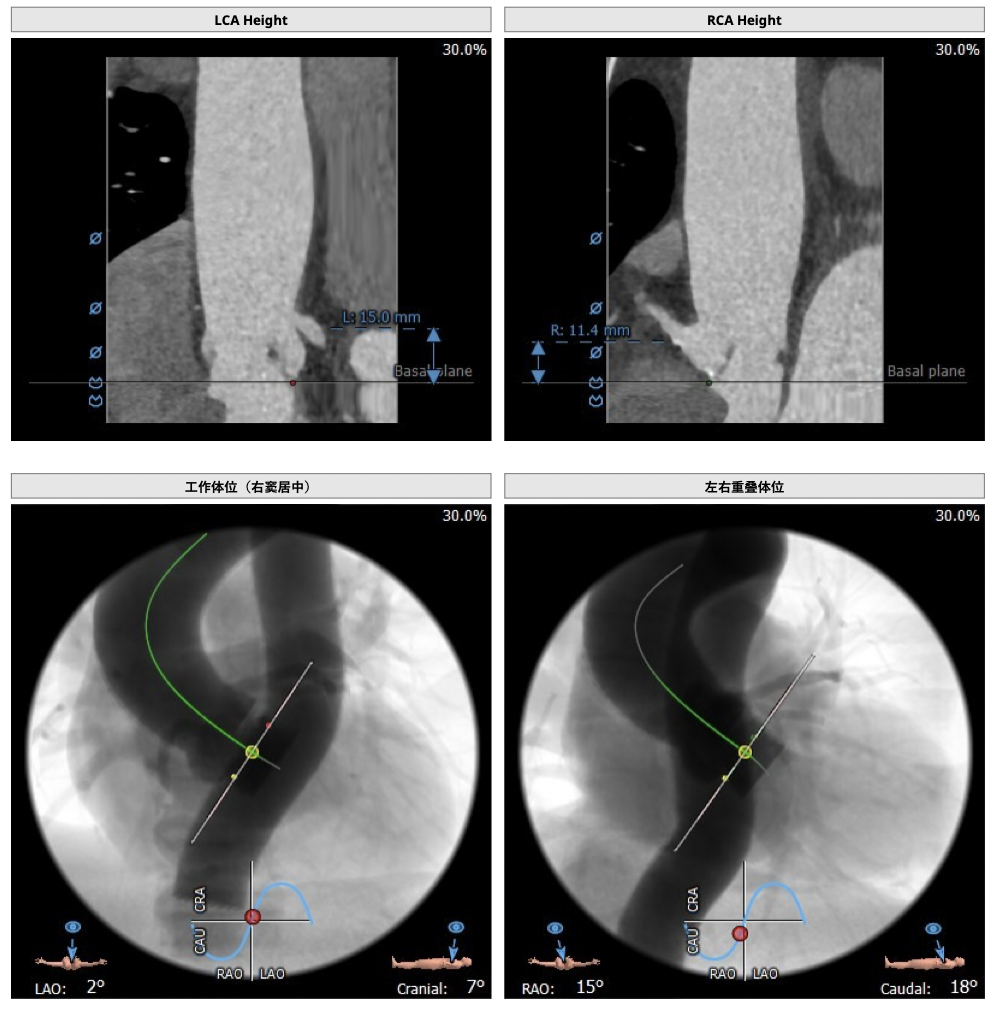

*患者为TYPE1型二叶瓣,左右融合,重度钙化,融合脊难以推开,瓣膜释放后具有一定瓣周漏风险;

*心脏角度为57°,横位心,输送器过瓣难度增加,瓣膜植入同轴性差,瓣膜释放更易移位,增加了操作的难度;

经分析研判,拟从右侧股动脉穿刺入路,使用20mm球囊预扩,采取downsize手术策略,选用L23号的VenusA-Valve瓣膜,因患者为横位心,瓣膜释放同轴性差,容易发生移位,故采用VenusA-Plus可回收输送系统确保瓣膜的稳定释放,瓣膜释放后结合造影和超声情况,决定是否后扩。